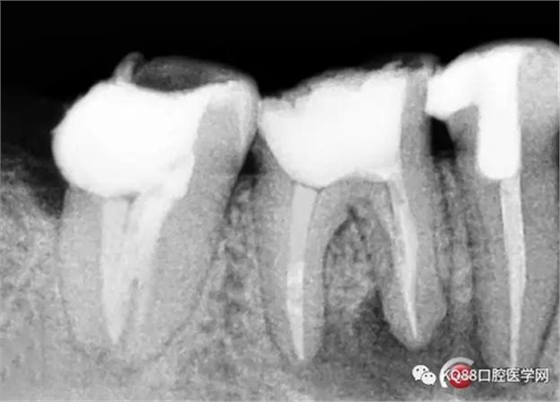

根充后X線片